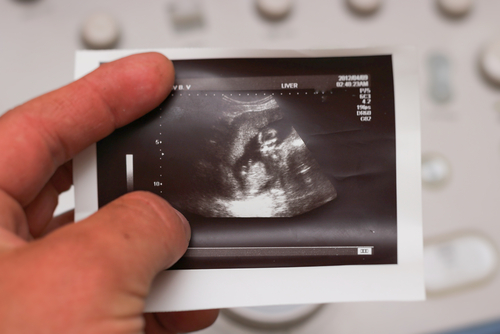

胎嚢は、赤ちゃんを包む膜のことです。エコー写真で見ると、ぽっかりと楕円形の黒い空間ができているのがわかります。妊娠が判明し、初期の検査でママが一番初めに目にすることができる、赤ちゃんの生存の証かもしれません。胎嚢は英語で「gestational sac」と言い、超音波検査の結果ではGSと表示されます。

胎嚢が初めて確認できるのは、妊娠4週の初めごろからです。正常な妊娠であれば、経腟超音波検査(エコー検査)で妊娠5週までには子宮内に胎嚢が確認できます(※2)。

妊娠が順調に経過していると、経腟エコー検査では妊娠6週頃、お腹の外から超音波をあてる経腹エコー検査では妊娠8週頃までに、胎児の心拍動があらわれます(※2)。ドップラー法を用いれば、妊娠12週目に胎児の心音を聞くことができますよ(※3)。